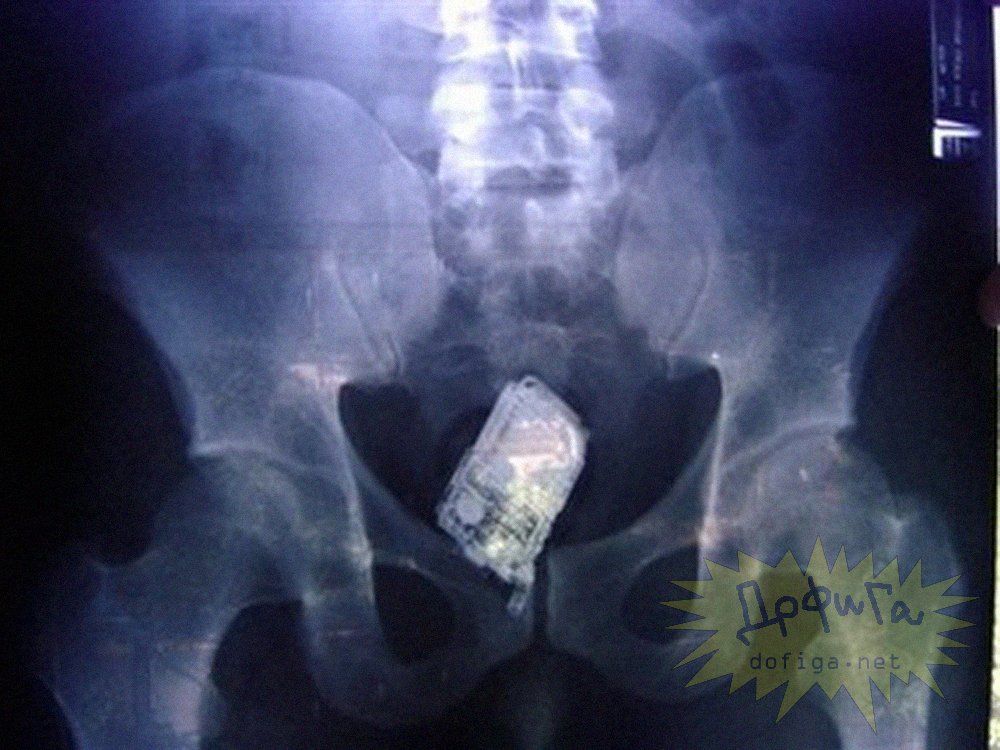

アナルに ”何かしら” を突っ込んで取れなくなってしまう人たちは意外に多いみたいで、そんな人たちのレントゲン写真を集めたギャラリー[13]images